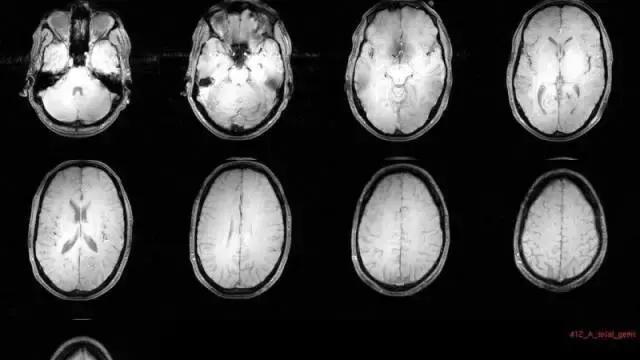

图 | CBF(脑血流量)

接着每名患者都接受了脑部扫描。研究人员发现,在某些区域(如杏仁核),脑血流量和脑活动都有所减少。话说在以前,科学家就曾表示杏仁核的活动与恐惧、焦虑的情绪反应相关。